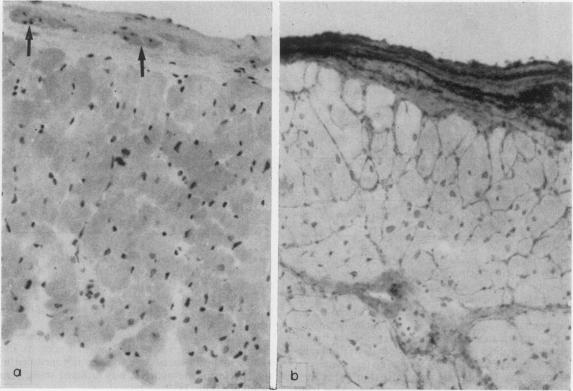

COCM的特殊检查:心内膜心肌活检(形态学分析)。

Special investigations of COCM: endomyocardial biopsies (morphological analysis).

Endomyocardial tissue obtained from 237 patients clinically suspected of suffering from congestive cardiomyopathy, has been analysed histologically, histochemically and ultrastructurally. In 51% of patients, the suspected diagnosis was morphologically confirmed and in 24.5%, no pathological evidence of a dilated heart or other pathology was found. The results in these two groups were considered helpful. It is concluded that, even though the morphology of congestive cardiomyopathy in non-specific and the number of other pathology found is small, the continuation of investigation by bioptome is justified. Parameters such as prognosis and length of history can also be assessed. Furthermore, morphological analysis is essential to interpret accurately biochemical and other types of investigations that are being carried out on biopsy material.

对237例临床疑似患有充血性心肌病患者的心肌内膜组织进行了组织学、组织化学和超微结构分析。51%的患者,疑似诊断在形态学上得到证实,24.5%的患者未发现心脏扩张或其他病理改变的病理证据。这两组的结果被认为是有帮助的。得出的结论是,尽管充血性心肌病的形态是非特异性的,且发现的其他病理改变数量较少,但通过活检继续进行研究是合理的。还可以评估诸如预后和病史长度等参数。此外,形态学分析对于准确解释对活检材料进行的生化和其他类型的研究至关重要。